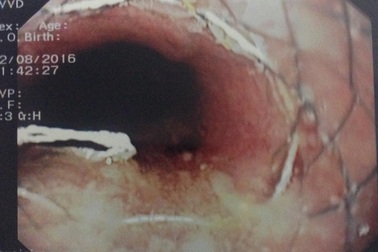

Xương gà xuyên thủng thực quản, bệnh nhân suýt tử vongNhập viện trong tình trạng sốt cao, đau tức ngực, ho khạc ra máu,… qua chẩn đoán hình ảnh, bác sĩ ghi nhận bệnh nhân bị hóc xương gà gây thủng thực quản. Không thể gắp xương bằng nội soi, bác sĩ buộc phải mổ cấp cứu lấy mảnh xương dài 3cm cứu bệnh nhân.

Suýt tử vong vì xương gà đâm thủng thực quản, phế quảnNhập viện trong tình trạng sốt cao, đau ngực, khó thở… qua chẩn đoán hình ảnh, bác sĩ ghi nhận bệnh nhân bị hóc xương gà gây thủng thực quản, phế quản. Không thể gắp xương bằng nội soi, bác sĩ buộc phải mổ cấp cứu lấy mảnh xương dài 3cm cứu bệnh nhân.